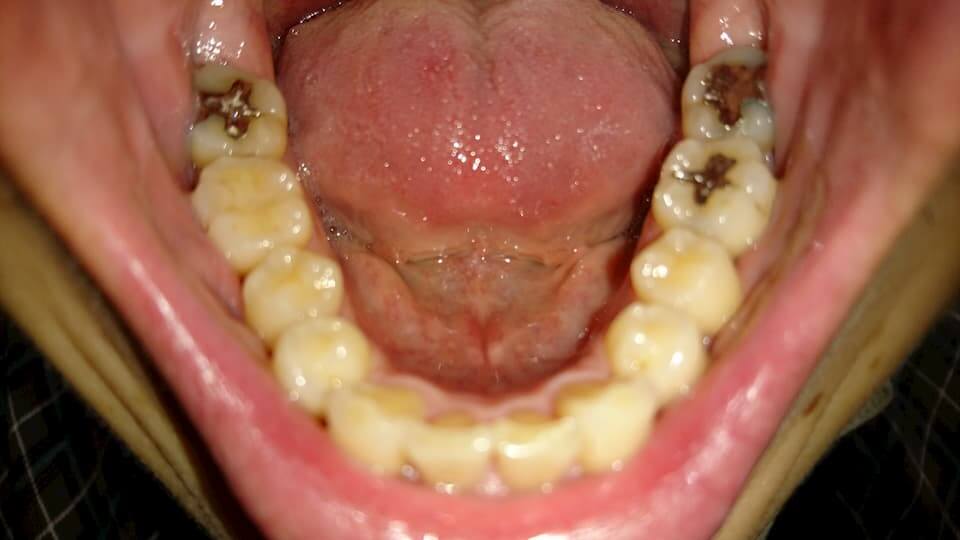

歯の写真